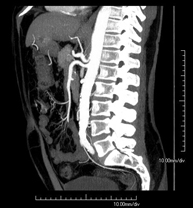

Abdominal aorta CT angiography

A non-invasive diagnostic test that involves studying the abdominal aorta by obtaining high-definition anatomical images using CT (computed tomography) equipment and iodinated contrast. With the aid of workstations specialised for arterial studies, the image quality supports 2D and 3D reconstructions. It is indicated in patients with vascular disease (atherosclerosis), aortic aneurysms, abdominal pain of possible vascular origin, pre-surgical studies of lesions adjacent to the abdominal aorta as a vascular ‘map’, etc. Information obtained non-invasively is indispensable for patients requiring percutaneous or surgical processing. In patients who only require tracking of vascular lesions, this technique is the non-invasive technique of choice, together with MRI angiography.